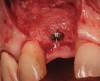

Figure 4  (Case 1) Implant removed and lingual bone maintained to receive augmentation.

Figure 4

Figure 5  (Case 1) Site augmented with a combination of demineralized freeze-dried bone allograft, non-resorbable and resorbable barrier.

Figure 5